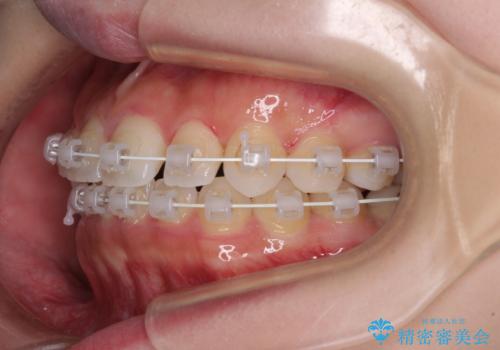

- 矯正装置

- 審美装置

- 治療期間

- 2年7ヶ月